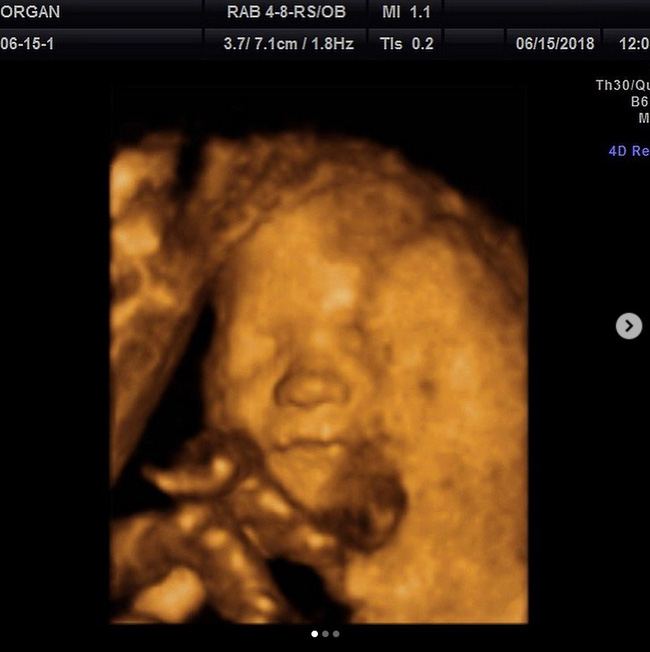

Bức ảnh siêu âm thai của Morgan vào tháng 6.

Cuối tháng 6, bé Emmy đã qua đời sau khi bị ngã xuống hồ bơi nhà hàng xóm. Vào thời điểm đó, Morgan đang mang thai một bé trai nữa trong bụng. Trước cái chết đáng thương của cô con gái bé bỏng, Morgan không còn tâm trí nào để đi siêu âm 3D cho thai kỳ. Thế nhưng, sau lời giới thiệu nhiệt tình của bác sĩ, cô thay đổi quyết định.

Trên bức ảnh hiện lên màn hình, Morgan thấy khuôn mặt của bé rất giống bố và các anh chị mình ở chiếc mũi và đôi môi xinh. Thế nhưng, khi liếc mắt sang phía bên phải, cô chợt thấy có hình ảnh mờ ảo giống như một khuôn mặt khác đang vòng tay ôm lấy em bé trong bụng. Ngay lập tức, Morgan nghĩ ngay tới Emmy. Cô có cảm giác như cô bé đã hóa thành thiên thần hộ mệnh che chở cho em trai mình.